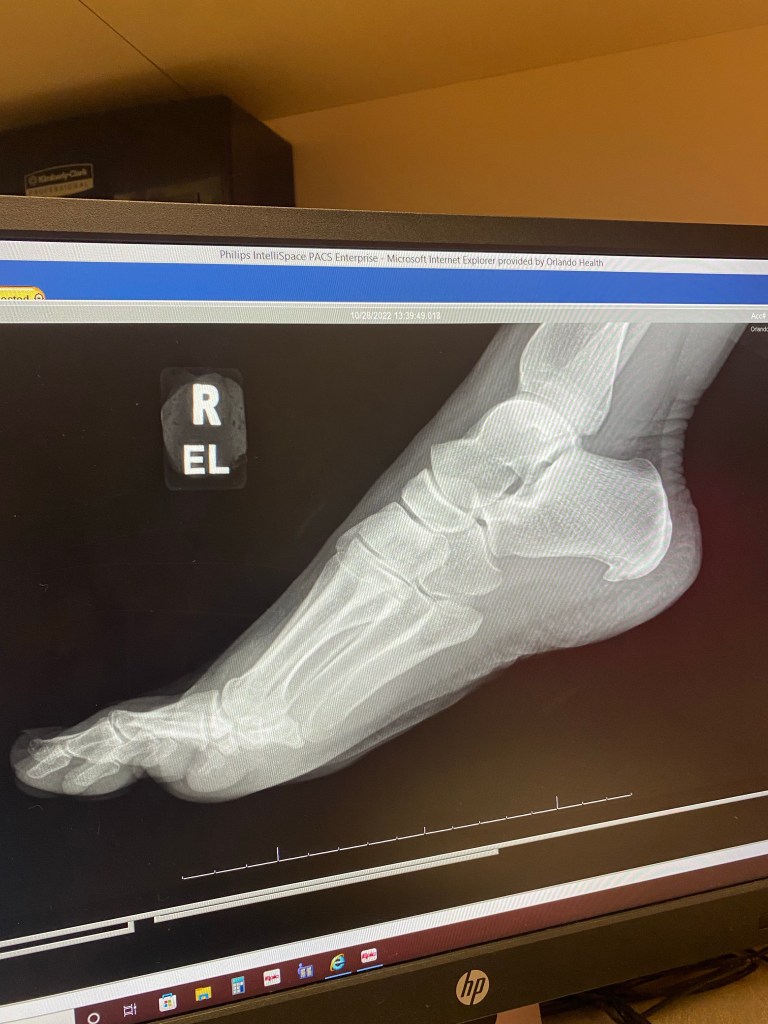

Well this is not how I wanted to jump back into this blog! 4 days ago I found out I have 2 fractures in my right foot…2 weeks out from the Sky to Summit 50k aka my “A” race of the season.

I went in for imaging because my last long run of 5 hours had to be shortened to 4.5 hours. I hobbled out a slow, but steady 20 miles that day but ended up in tears due to foot pain in the last 30 minutes. That’s the point, in my gut, that I knew something was off.

Fast forward 3 days later, and I felt a pop as I stepped forward after completing a fabulous 4 mile run. My foot started to hurt very bad and began to swell immediately. Denial, and a bit of panic, began to set in. Last night I officially withdrew from the event.